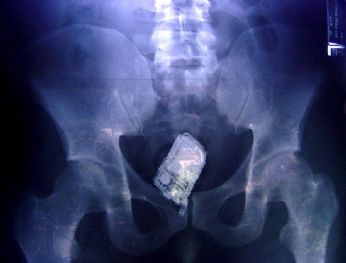

domenica 15 aprile 2007 - ore 13:55 Qualcuna si lamentava della mancanza di colori ![]() ![]() LEGGI I COMMENTI (4) - PERMALINK sabato 14 aprile 2007 - ore 11:34 Maglietta Joy Division ![]() ![]() LEGGI I COMMENTI (4) - PERMALINK venerdì 13 aprile 2007 - ore 16:52 Oggi è Venerdì 13... me ne sono accorto adesso ![]() ![]() COMMENTA (0 commenti presenti) - PERMALINK venerdì 13 aprile 2007 - ore 08:53 Dove nascondere la refurtiva ahuhahuahuauh ![]() COMMENTA (0 commenti presenti) - PERMALINK giovedì 12 aprile 2007 - ore 13:10 Dai, non pensarci troppo cos’è??è facilissimo! la cantano 2 pesci..che in realtà non sono pesci dopo diventano anche scoiattoli.. Si trasformano pure in uccellini e il più piccolo prende lezioni di volo da un gufo..ANACLETO.. LEGGI I COMMENTI (9) - PERMALINK mercoledì 11 aprile 2007 - ore 20:07 Anteprima maglietta Depeche Mode di (quasi) mia produzione ![]() LEGGI I COMMENTI (2) - PERMALINK mercoledì 11 aprile 2007 - ore 13:34 Anteprima maglietta Joy Division di (quasi) mia produzione COMMENTA (0 commenti presenti) - PERMALINK |